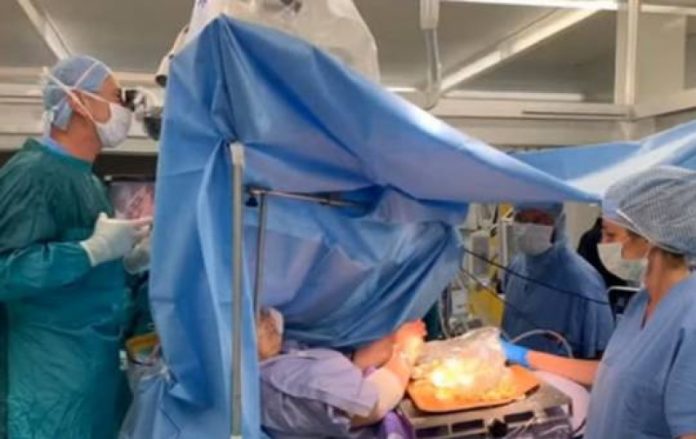

Pacijentica u Italiji čistila masline dok su joj odstranjivali tumor sa mozga

Hirurzi od pacijenata obično traže da, za vrijeme operacije na mozgu sviraju violinu ili gitaru, no šezdesetogodišnja Italijanka je za…